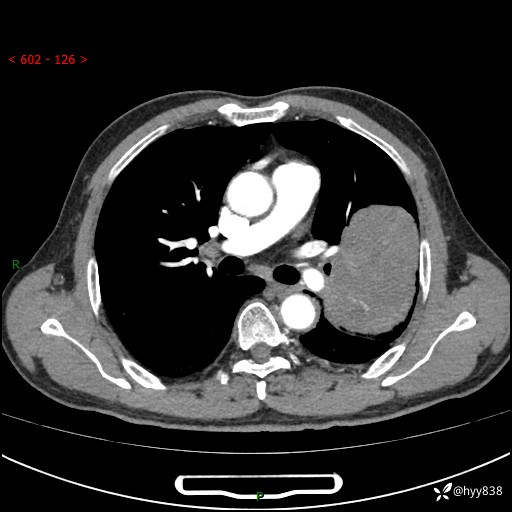

68岁/男,发现左下肺占位5天。如此大的肿块,患者竟然没有症状---结果公布~

【患者信息】:68岁/男

【主诉】:检查发现左下肺占位5天。

【现病史及既往史】:患者于4天前外院行“经尿道钬激光碎石术”,住院期间胸部CT检查发现左下肺肿块,患者平素无明显咳嗽咳痰,无心慌、胸闷、胸痛、呼吸困难、低热、盗汗,无头痛、头晕,无腹痛、腹胀等不适,现患者为求进一步治疗,遂来我院就诊,以“左下肺肿块”收入我科。 患者自起病以来,精神可,睡眠可,饮食可,大小便正常,体重无明显改变。

【检查】:胸部CT增强扫描